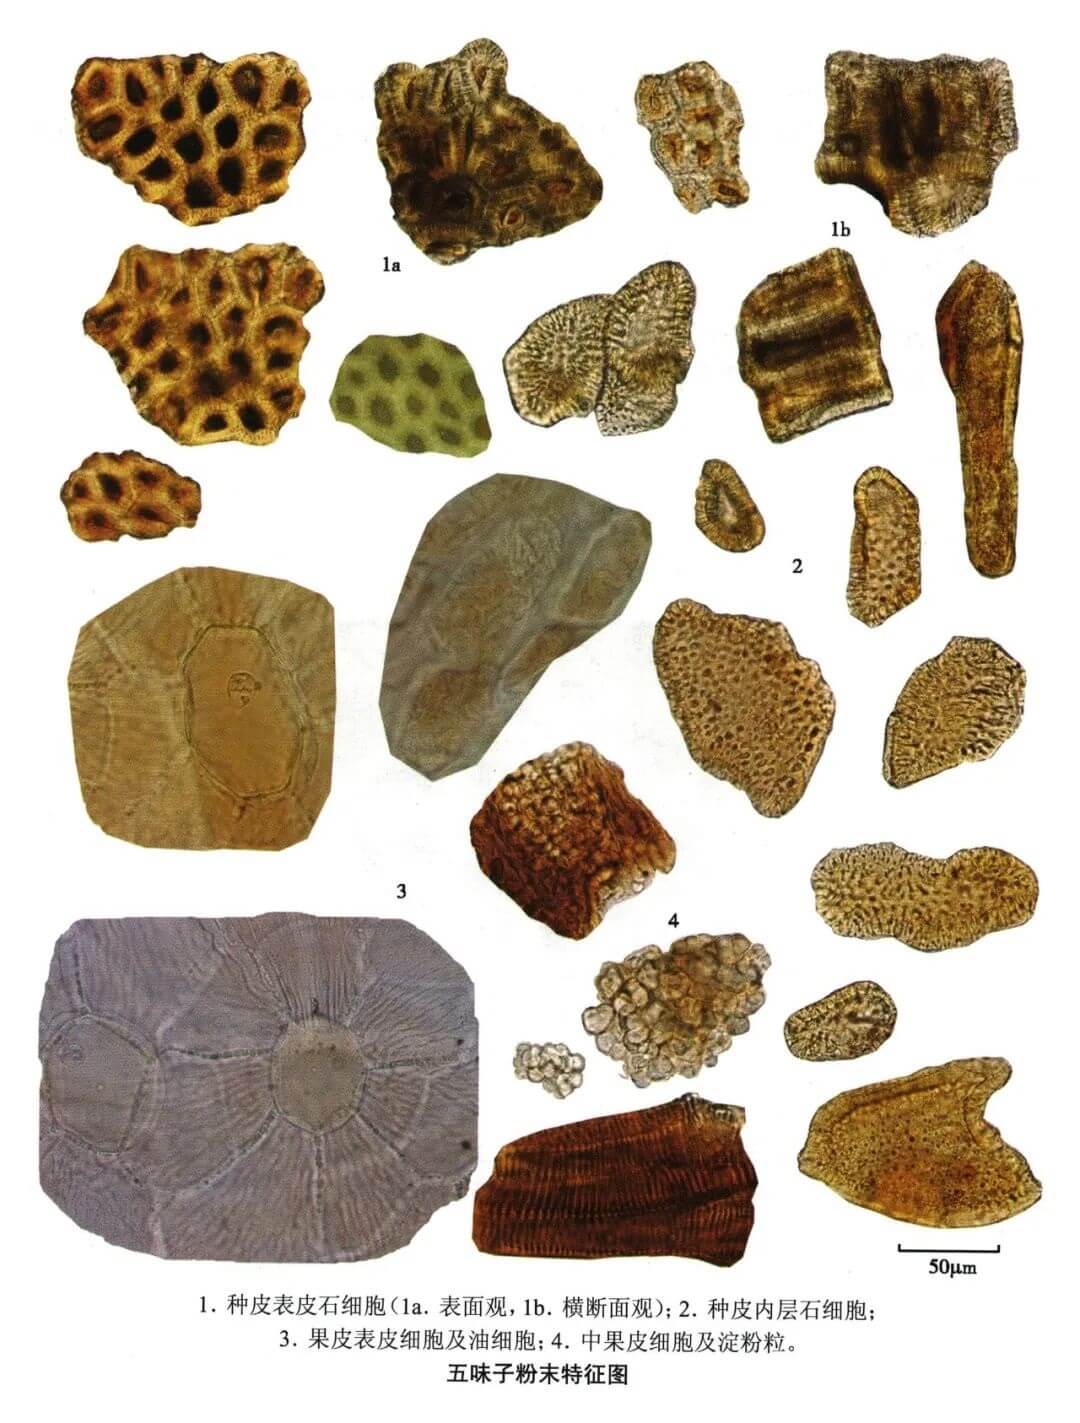

五味子

| 五味子 |

|---|

| 【参考标准】 《中国药典》2020年版 一部 |

| 【显微鉴别】 粉末暗紫色。种皮表皮石细胞表面观呈多角形或长多角形,直径18~50μm,壁厚,孔沟极细密,胞腔内含深棕色物。种皮内层石细胞呈多角形、类圆形或不规则形,直径约至83μm,壁稍厚,纹孔较大。果皮表皮细胞表面观类多角形,垂周壁略呈连珠状增厚,表面有角质线纹;表皮中散有油细胞。中果皮细胞皱缩,含暗棕色物,并含淀粉粒。 |

| 【显微重点】 果皮表皮细胞表面观、种皮表皮石细胞及种皮内层石细胞。 |

| 【图谱来源】 《中药成方制剂显微图典》 |